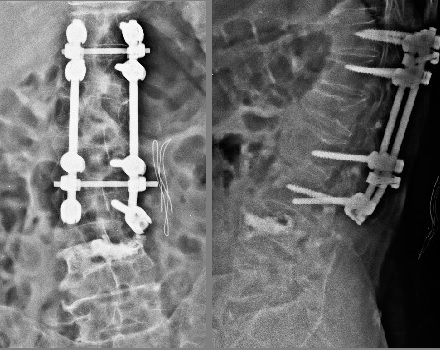

Bilgisayarlı

tomografide L3 seviyesinde sağda vida gevşemesi (vida etrafında

sklerotik halo), L4 vertebrasında ön ve orta kolonda yükselik kaybı,

korpusa ve sol pediküle uzanan kırık hatları ve ayrıca bu

seviyede

solda belirgin olarak faset eklemlerde ayrışma görülmekte.

Sisteme ait diğer vidalar gevşememiştir. L2-3 seviyesinde kısmi,

yukarıdaki seviyelerde tam faset füzyonu vardır.